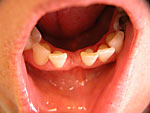

Die folgenden Patientenfälle sollen Ihnen einen Einblick in die Möglichkeiten der modernen Implantation geben.

Implantation – Patientenbeispiel 1: